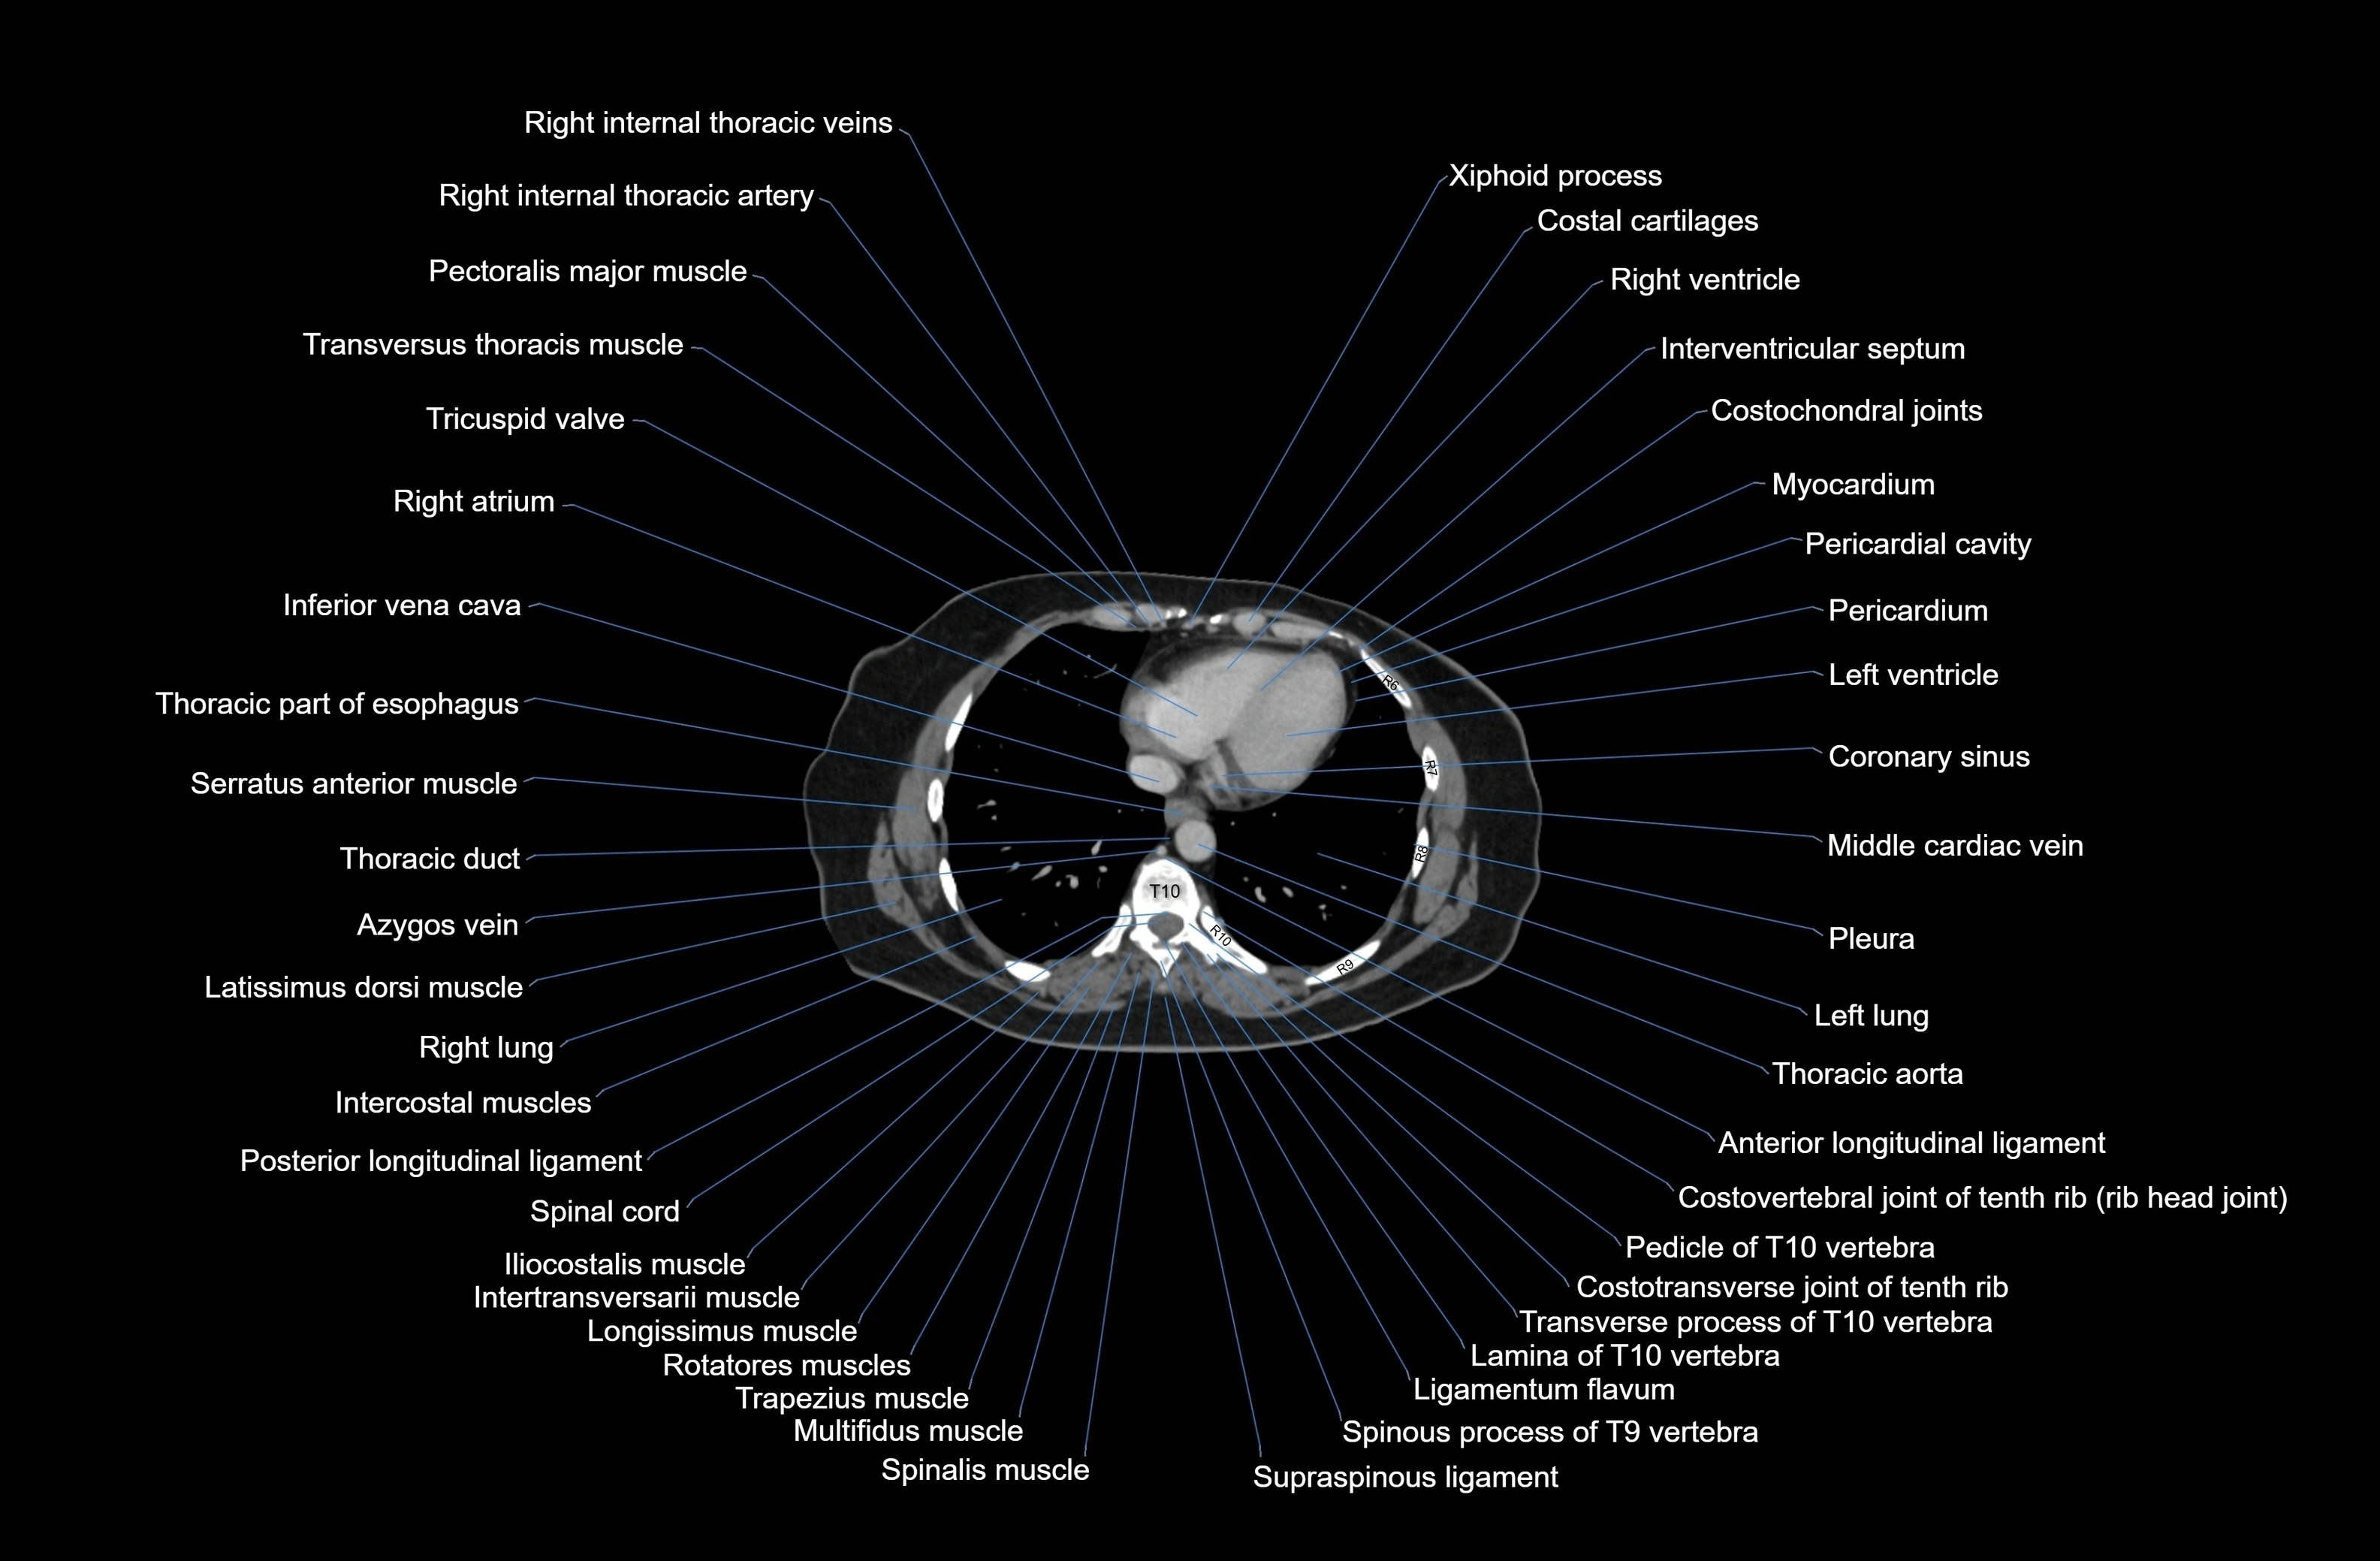

CT images